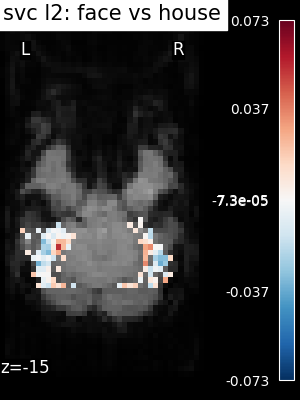

svc(same assvc_l2) : The support vector classifier.svc_l1: SVC using L1 penalization that yields a sparse solution : only a subset of feature weights is different from zero and contribute to prediction.logistic(orlogistic_l2) : The logistic regression with l2 penalty.logistic_l1: The logistic regression with l1 penalty (sparse model).ridge_classifier: A Ridge Regression variant.dummy classifier: A dummy classifier is a classifier that makes predictions using simple rules. It is useful as a simple baseline to compare with other classifiers.

The SVC-l2 is fairly insensitive to the choice of the regularization parameter which makes it a good and cheap first approach to most problems

The corresponding weight maps (below) differ widely from one estimator to the other, although the prediction scores are fairly similar. In other terms, a well-performing estimator in terms of prediction error gives us little guarantee on the brain maps.